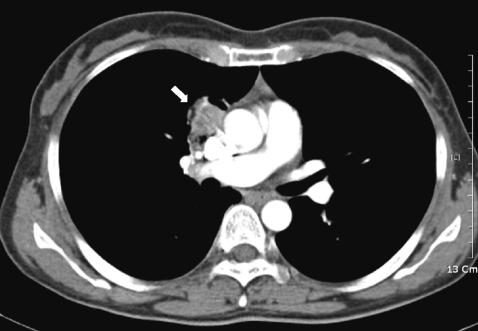

On July, the patient revisited our department because of hemoptysis and chest discomfort. A roentgenogram and CT conducted at that time showed an approximately 3.2×2.8 cm heterogeneously enhanced mass-like consolidation in the anterior segment of the right upper lobe, which was attached to the mediastinal pleura (Fig. 1). The patient underwent a percutaneous needle biopsy of this lung lesion. The histologic findings showed abundant inflammatory cells, including many eosinophils, some granulomas, and necrotic cellular debris (Fig. 2). Parasitological examination of the stool and sputum showed negative results. Triclabendazole-resistant paragonimiasis was strongly suspected on the basis of the persistent eosinophilia (WBC 6.05×103 cells/mm3, eosinophils 27%), radiological findings of the lung (Fig. 1), and histologic findings (Fig. 2). The P. westermani-specific IgG titer (OD: 0.77) was not decreased compared with that noted in October, 2008 (Fig. 3).